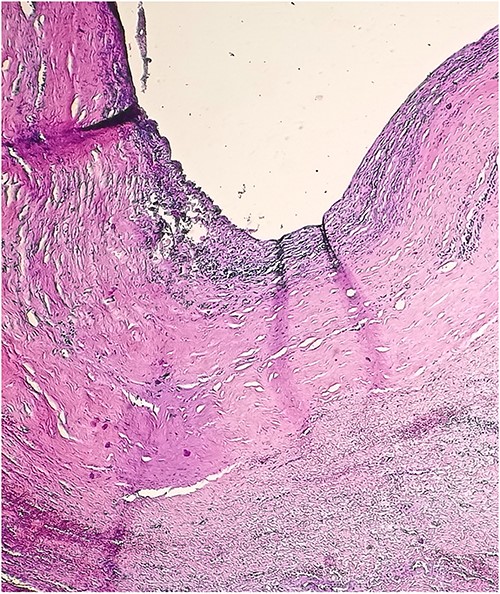

A 46-year-old male presented with mild abdominal pain for the last 2 months. The pain was generalized, recurrent and did not relieve on medication. The patient showed intermittent claudication in his right leg. He presented with a similar complaint five years ago; abdominal pain and urinary urgency and hesitancy, which led to a diagnosis of a simple abdominal cyst. Past medical history was insignificant. Surgical history included retroperitoneal cystectomy, herniorrhaphy and a cleft palate repair. Patient had no other complaints and was not on any medications. He was a smoker with a 22 pack-year smoking history. His temperature was normal, and there was no history of weight loss or loss of appetite or change in bowel movement. On physical examination, the abdomen was soft and non-tender without distention. There was a palpable mass in his right flank. Vital signs and blood tests were within normal limits. Abdominal ultrasound (US) showed a large fluid-filled cystic lesion (Fig. 1a). Subsequent computerized tomography (CT) of the abdomen showed a large, well-defined, clear fluid-filled cyst measuring 17 × 11 × 10 cm, located in the retroperitoneum abutting the lower half of the right kidney, extending to the pelvis and compressing the inferior vena cava (Fig. 1b). Patient was cleared for surgery. Surgical exploration showed several adhesions surrounding the cyst. The cyst was partially isolated from the right ureter and iliac vein and artery (Fig. 2a and b), then surgical excision of 90% of the cyst was performed (Fig. 3). Histopathological report found the cystic wall composed of fibrous connective tissue and lined by one layer of flat cells, with mild lymphocytic infiltrate and congested blood vessels confirming the diagnosis of a chylolymphatic cyst (Fig. 4). On a 1-year follow-up, the patient appears to be recovered and in good health with no recurrence.

Accordingly, the findings of this case suggest a chylolymphatic cyst of traumatic origin, considering the histopathologic features of the cyst wall consisting of fibrous connective tissue and infiltrated by lymphocytes and congestive blood vessels, and a history of a surgical intervention on the same location resulting in trauma to the lymphatic channels.